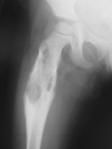

Parathormon kalsiyum dengesinin düzenlenmesinde önemli rol oynar. Hiperparatiroidizim sonucu parathormon aşırı salgılanır ve artan osteoklast aktivitesi sonucu iskelet değişiklikleri meydana gelir. Ciddi kemik erimelerine ve kemiklerde büyük kistik lezyonlar oluşmasına yol açar. Radyografideki görüntü, sınırları belirsiz, kemiği genişleten, litik lezyonlardır. Dev hücreli tümör görüntüsüne benzer, ancak epifizden çok diyafizi tercih ederler.

Hastada kanda, kalsiyum, fosfor, alkalen fosfataz, parathormon seviyesinin yüksekliği ve lezyondan alınan biyopsi ile tanı koyulur. Histolojik bulgular dev hücreli kemik tümörü ile karışabildiğinden ayırıcı tanıda dikkatli olmak gerekir.

Tedavi kemiği yükten koruyarak kırılmaların engellenmesi ve esas sorunun kaynaklandığı paratiroid bezi hastalığının tedavi edilmesidir. Bu şekilde kemiğe uygulanacak gereksiz cerrahiler engellenebilir. Uygun tedaviden sonra kemik lezyonları kendiliğinden iyileşecektir. Ortopedik olarak kırık ve kırık riski mevcut ise ameliyat yapılır.